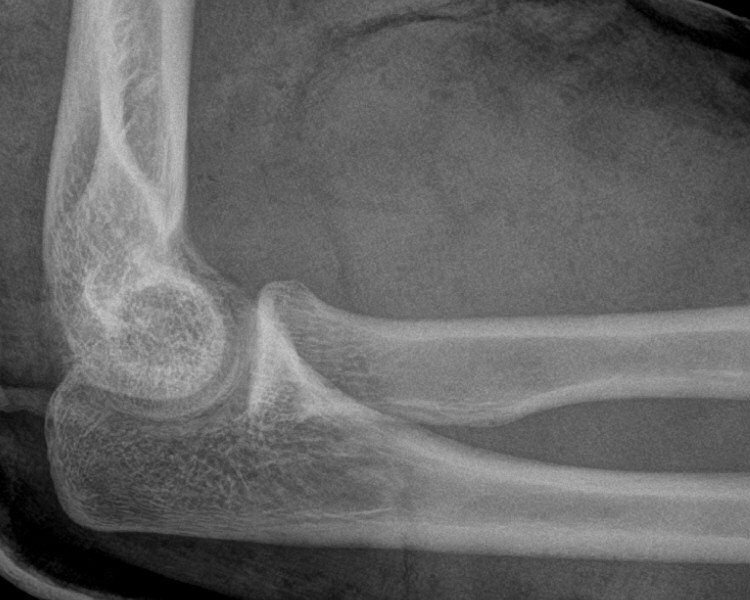

På röntgenbild ska radius längsaxel normalt gå centralt igenom capitellum humeri i både frontal- och sidobild av armbågen. Vid luxation:

Luxerad caput radii, ingen fraktur i ulna, på andra bilden reponerad och gipsad